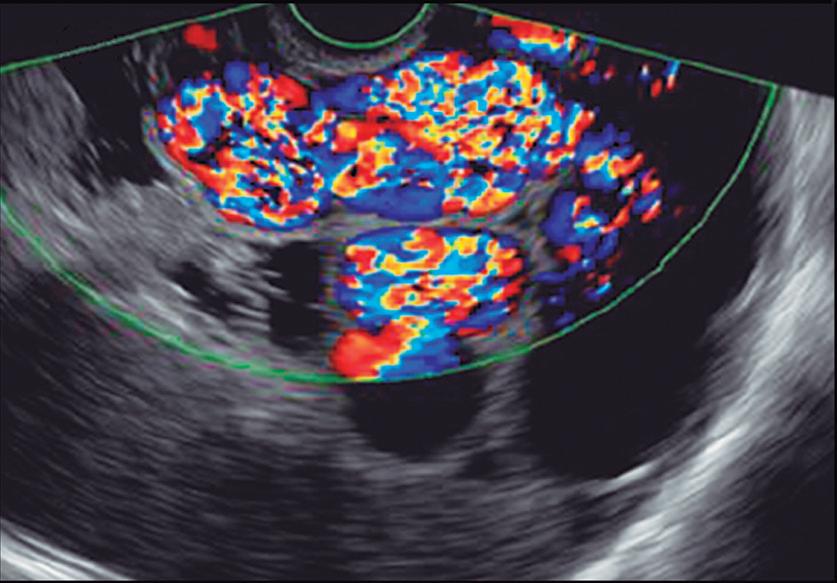

La endoscopía superior es un procedimiento fundamental para el diagnóstico, la evaluación de la respuesta al tratamiento y el monitoreo a largo plazo de la actividad de la EEo. Los hallazgos endoscópicos típicos incluyen edema (reducción de vascularidad), anillos esofágicos fijos, exudados blancos, surcos longitudinales, estenosis, estrechamiento de la luz esofágica, friabilidad de la mucosa (mucosa en papel crepé) y una consistencia firme de la mucosa al realizar biopsias (signo de “tracción" o "resistencia”) en pacientes con fibrosis (Figura 1). Estos hallazgos no son patognomónicos y no constituyen un criterio diagnóstico; sin embargo, cuando se evalúa de forma cuidadosa, en la gran mayoría de los casos se pueden observar.19-21

En el panel A se observa un esófago con edema difuso y pliegues longitudinales; en el panel B se aprecia edema con pliegues y exudados blanquecinos; en el panel C se evidencia un estrechamiento luminal acompañado de anillos esofágicos y exudados; y en el panel D se muestra un desgarro mucoso posterior a la dilatación con bujía de Savary, hallazgo esperado tras este procedimiento terapéutico.

Figura 1. Características endoscópicas de la esofagitis eosinofílica